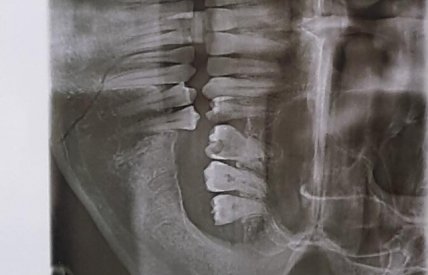

Цыгане напали и избили своих оппонентов. В результате у ветерана АТО диагностировали переломом челюсти, ушиб волосистой части головы и травмы мягких тканей головы.

рентген